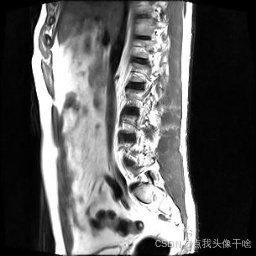

想象一下,你给AI看一张脊椎的核磁共振(MRI)照片,它就能像经验丰富的医生一样,把照片里每一块骨头、每一节椎间盘都给你清清楚楚地标记出来。这个系统干的就是这个酷炫的事儿!

- 原图:就是一张张脊椎的MRI扫描图。